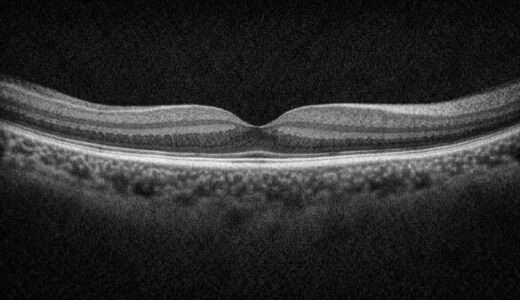

ICGで見えているのは、FAでは見えないRPEより奥にある脈絡膜の血管です。

つまり、網膜の下の構造――特に脈絡膜の中大血管レベルまでしっかり観察できるのがICGの特長です。

OCT-Aでも脈絡膜の浅層(主に脈絡膜毛細血管層)までは見えますが、脈絡膜中層以深の中大血管まではカバーしきれません。

一方、ICGでは脈絡膜全体(特に中大血管)を動的に観察できるため、ポリープ様病変(PCV)や脈絡膜新生血管の詳細な評価にはICGの方が優れています。